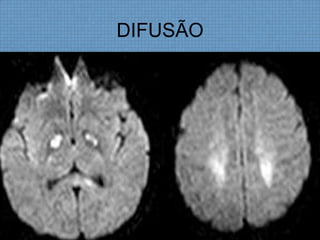

ACHADOS DE IMAGEM

– Restrição à difusão indica irreversibilidade do dano neuronal;

INTOXICAÇÃO POR CO

INTOXICAÇÃO SUICIDA-3H

• Hemorragia Palidal aguda bilateral;

DIFUSÃO